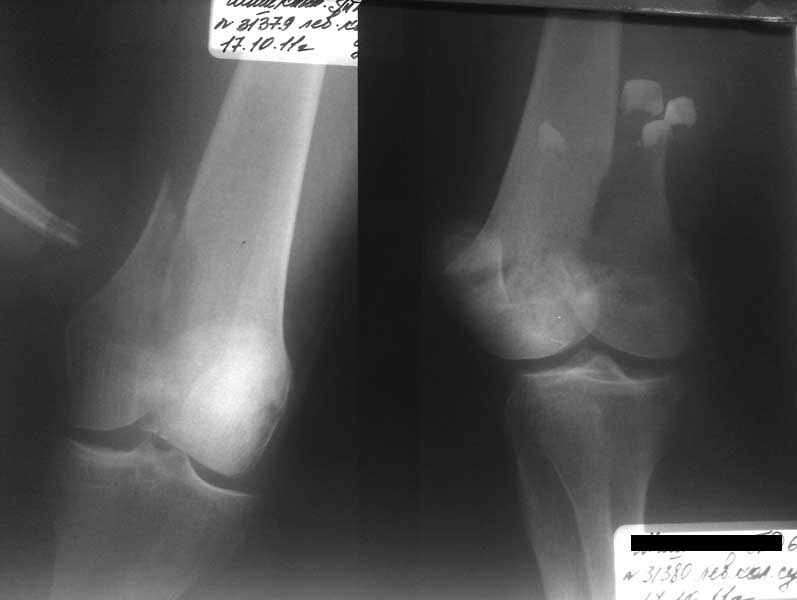

Остеосинтез, вестимо. КТ предварительно можно сделать, чтобы поточнее увидеть повреждения в межмыщелковой области. Перелом ближе к 33C1.

Похоже что перелом простой как по суставной поверхности так и по метафизу (тип 33-C1). В таком случае возможно МОС (в порядке уменьшения стоимости): дистальной бедренной LCP (в прошлом LISS-DF); DCS; угловой клинковой пластиной 95 градусов. Все перечисленные импланты возможно установить как с традиционного доступа, так и менее инвазивно (из двух/один+протоколы). Технику можно найти в (в порядке уменьшения новизны): AO Surgery reference; Tong; Ruёdi, Мюллер.

Представленный снимок не дает полную информацию. Там вроде простой перелом, но на самом деле, кроме смещенного (латерального, возможно медиального?) мыщелка на второй проекции имеется медиальный короткий дистальный фрагмент в флексии. Надо было сделать прямой снимок с захватом малоберцовой, который ориентировал бы стороны. Без КТ обычный снимок в дистракции поможет разобраться в топографии фрагментов.

Во время фиксации надо соблюдать осторожность, особенно с коротким фрагментом на другой стороне. Обычно на прямой проекции трудно заметить флексионную деформацию мыщелка и упускается адекватная фиксация. Без пластины винты не смогут удержать, и мыщелок на второй стороне может сместиться. Для фиксации надо развернуть мыщелок и удержать винтами. Качество межмыщелковой репозиции надо проконтролировать артротомией. Из всех доступов только передне-латеральный доступ (Swashbuckler) даст обзор для ревизии качества фиксации, который в будущем может быть использован для артропластики.

Кстати, из вашего снимка, если отмечены вашим рентгенологом правильно, тогда получается снимок левого колена, и, соответственно, длинный переходящий в диафиз мыщелковый фрагмент находится медиально. Если так, тогда меняется сценарий фиксации!!!

Сразу не обратил ваше внимание именно на это, что сломаны оба мыщелка, и больший является именно медиальным мыщелком, а пластины ставятся по латеральной стороне, соответственно, в этом медиальном мыщелке от пластины останутся только концы винтов, которые не обеспечат достаточной фиксации мыщелка.

И не обратите, коллега, пока не сделаете четкие анфасные снимки (лучше с дистракцией) где будет четко визуализироваться малоберцовая кость. Думается, что и КТ здесь будет уместно, дабы не пропустить возможное флексионное повреждение (перелом Hoffa).